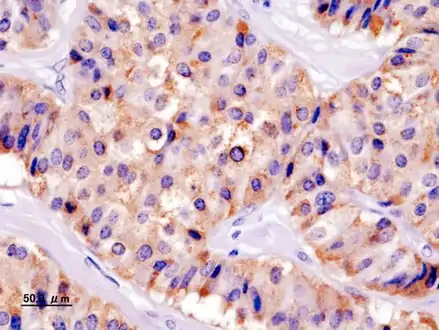

Pancreatic insulinoma

Chromogranin A

Insulin immunostain